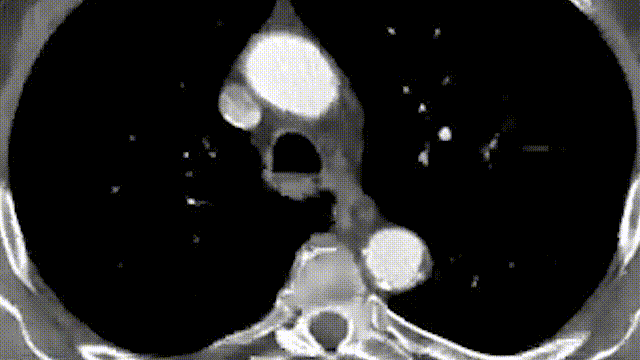

Beckerman教授分享了一例腹主分支激光原位开窗病例报道。患者是一名79岁的男性,术前CTA显示该患者为Ⅳ型胸腹主动脉瘤,直径为6.2cm。